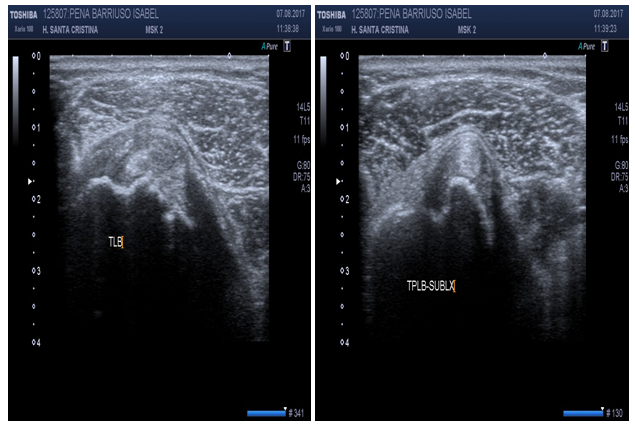

US can ascertain between normal versus diseased bicipital tendon (partial or full tears, tendinosis). Hyperechoic “fluid ring” around tendon may denote tenosynovitis in short axis, whether a “tear sign” may denote tenosynovitis in long axis (Figure 14). US may identify osteophytes in AC joint and joint effusion (“Geyser Sign”) if inflammation subsides (Figure 15). Small calcific areas in the tendon can be observed specially when assessed dynamically (Figure 16). US is highly sensitive to diagnose SASD bursitis, especially if fluid on scan image is greater than 2mm distance (Figure 17). Dynamic evaluation is capable to determine biceps tendon subluxation or luxation and subacromial impingement (Figure 18).

Figure 18 Dynamic evaluation that demonstrates subluxation of biceps tendon after external rotation of shoulder.